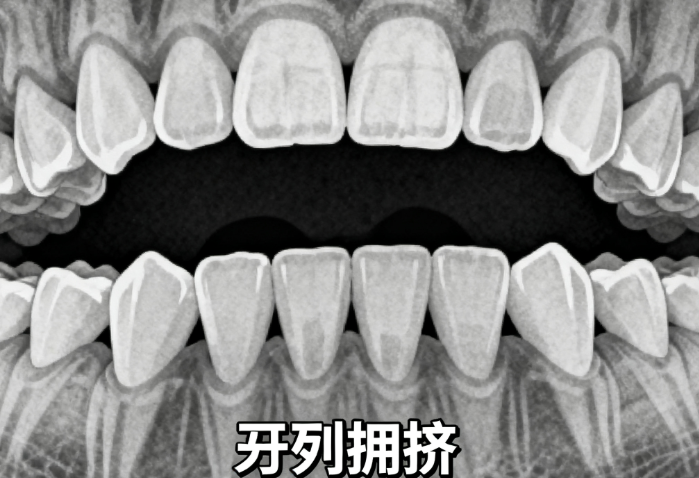

四川友谊医院牙齿矫正多少钱不同方案价格对比分析,隐形矫正与传统矫正价格差异有多大?

四川友谊医院牙齿矫正价格大致在1万到8万元之间,具体费用因矫正方式、牙齿问题复杂程度和是否需要配合正颌手术而有所不同。金属牙套约1万元,隐形牙套2万到5万,复杂情况可能需要正

钦州市牙齿矫正多少钱?隐形矫正比传统贵3000元

2026年钦州市牙齿矫正价格范围从5000元到80000元不等,具体费用受矫正方式、医院等级、医生经验等因素影响。传统金属托槽矫正价格在8000到15000元之间,适合预算有限的患者;隐形矫正